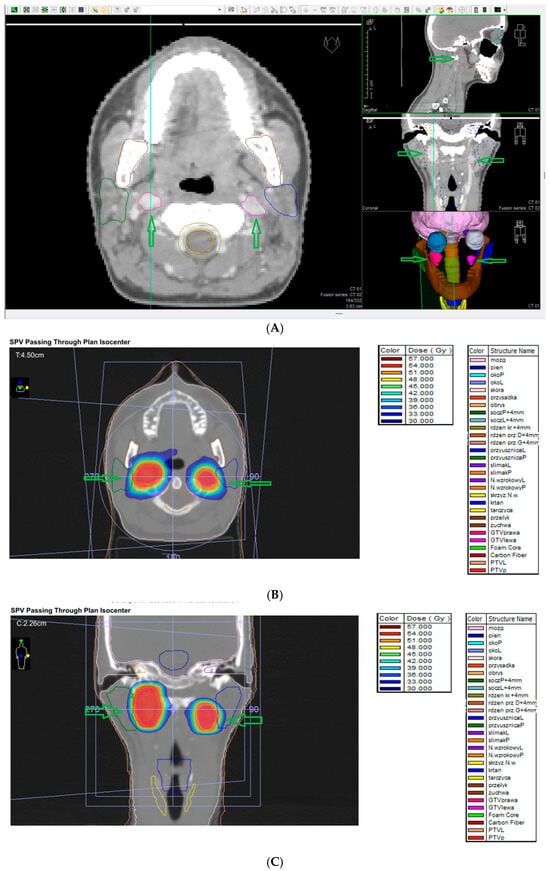

7.8. Stereotactic Radiosurgery (SRS)

7.9. External Beam Radiotherapy (ERBT) and Hypofractionated Stereotactic Radiotherapy (hSRT)